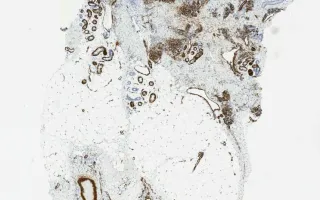

Blood vessels, tufted hemangioma, SMA stain

Tufted hemangioma

13 month old male infant with a tumour on the shoulder.

Tufted angiomas are benign vascular lesions which often occur on the neck or shoulders of children or young adults. Microscopically, they are comprised of nodules of tightly packed capillaries which may involve the dermis and superficial subcutis. Crescentic cleft-like vessels or semilunar lymphatic channels are generally seen at the periphery of some of the capillary tufts (nodules). These vessels are lined by unremarkable endothelial cells (CD31 positive) and surrounded by pericytes (smooth muscle actin positive). D2-40, a marker of lymphatic endothelial cells, is expressed in the crescentic cleft like vessels, but the proliferative capillaries are negative. The capillary lumina are not readily evident in many areas. GLUT-1 was negative in this case; it is positive in juvenile hemangiomas.

This slide shows SMA stain, see Related Content for H&E, CD31, and D2-40 stains.